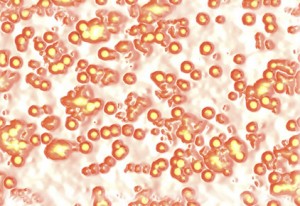

Il collegamento tra bocca e apparato respiratorio è più diretto di quanto si pensi. In presenza di placca o igiene inadeguata, i batteri orali possono essere inspirati e colonizzare le vie aeree inferiori, soprattutto negli anziani o nei pazienti allettati. Nei soggetti intubati, la comunicazione fisica tra cavo orale e vie respiratorie diventa una porta aperta all’infezione. Ma non si tratta solo di un passaggio meccanico: l’infiammazione cronica delle gengive stimola la produzione di molecole che circolano nel sangue e aumentano la risposta infiammatoria sistemica, peggiorando anche patologie respiratorie preesistenti.